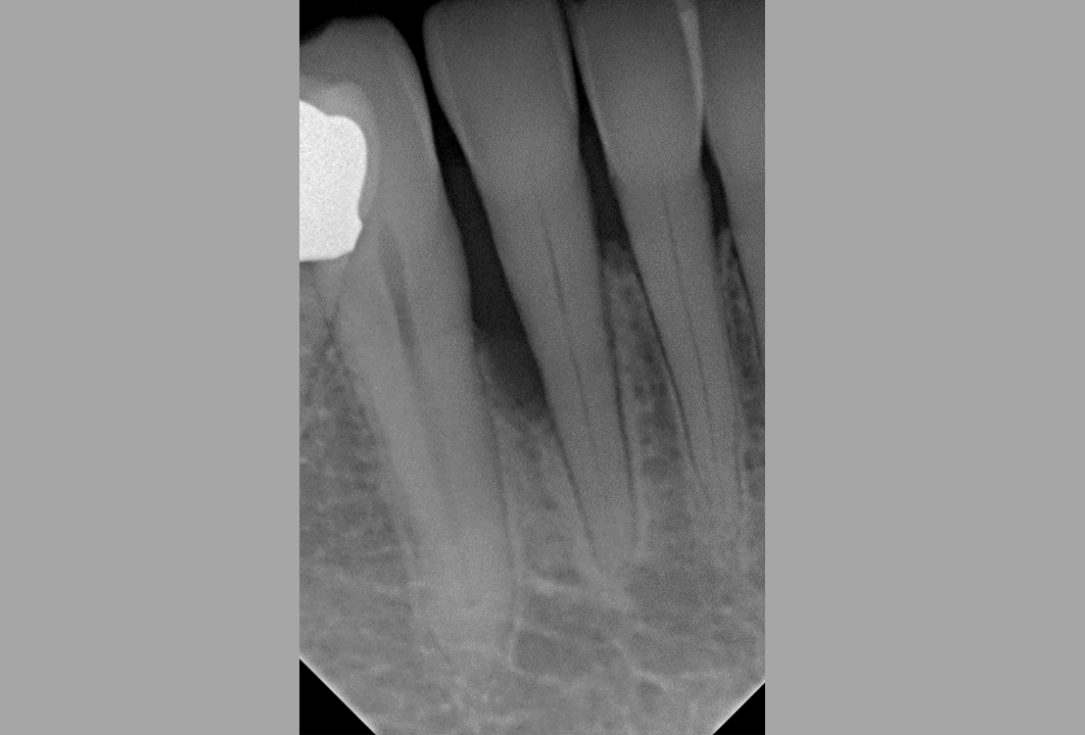

02/08 - Pre-surgical probing reveals a deep intrabony defect on the distal aspect of tooth 42.

Non-contained intrabony defect treated using Straumann® Emdogain® and a synthetic bone grafting material - Prof. Dr. Dr. A. Kasaj

03/08 - Radiograph showing a deep intrabony defect on the distal aspect of tooth 42.